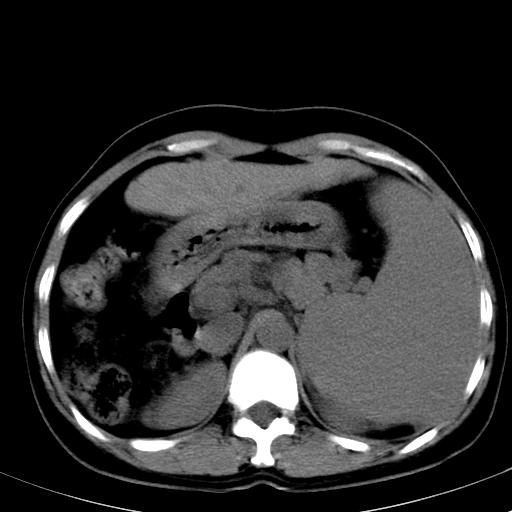

标题: CT19818:女40,脾大伴贫血,无肝炎病史 [打印本页]

标题: CT19818:女40,脾大伴贫血,无肝炎病史

血常规血红蛋白102,

骨穿,诊断再障,无其他病史

脾大符合临床诊断(再障)。

巨脾。

肝硬化、门脉高压、脾大。再障+肝硬化促成巨脾。

肝叶比例失调,肝左叶明显增大,包膜欠规整,脾大,支持考虑肝硬化、门脉高压、脾大。